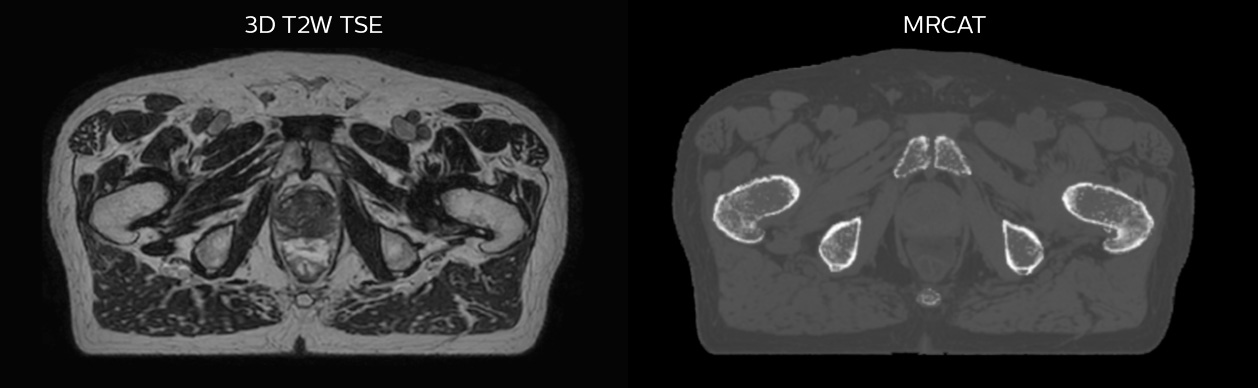

Prostate MR-only radiotherapy planning with use of rectal spacer

Hôpital de La Tour uses an implanted rectal spacer (SpaceOAR®, Boston Scientific) for patients receiving prostate radiotherapy to provide space between the rectum and prostate. 3D T2W TSE MRI provides excellent rectal spacer visualization and is used for OAR and target contouring. The dose plan is calculated on the MRCAT dataset.

Simulation imaging

Tranversal 3D T2W TSE with Compressed SENSE, acquired on Ingenia MR-RT 1.5T (left).

On-console generated MRCAT (right).

MR-based contouring and planning

MRCAT is primary image dataset for dose calculation (left).

3D T2W TSE MRI with 36 cm Field-of-View is used for delineation of prostate and organs at risk (right).